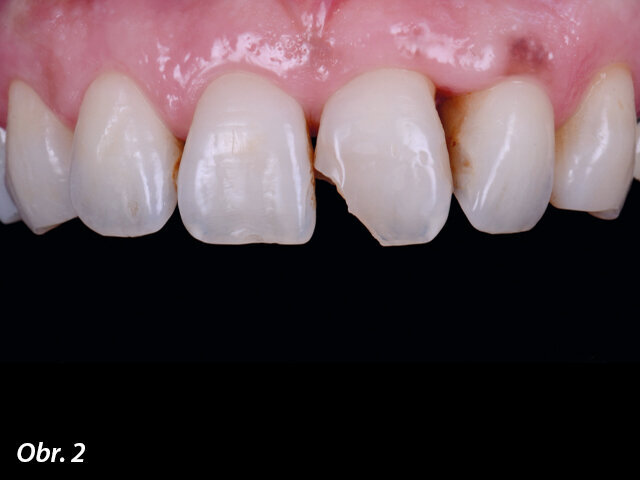

40letá celkově zdravá pacientka se dostavila na akutní ošetření. Pádem na konferenční stolek si urazila meziální růžek zubu 21, přičemž fraktura zasahovala až do střední třetiny zubu. Na zkoušku vitality reagoval zub pozitivně. Vzhledem k barvě a textuře, kterou bylo třeba reprodukovat, byla pacientka objednána na anatomickou stratifikaci.

Kazuistika 1 – výchozí stav.